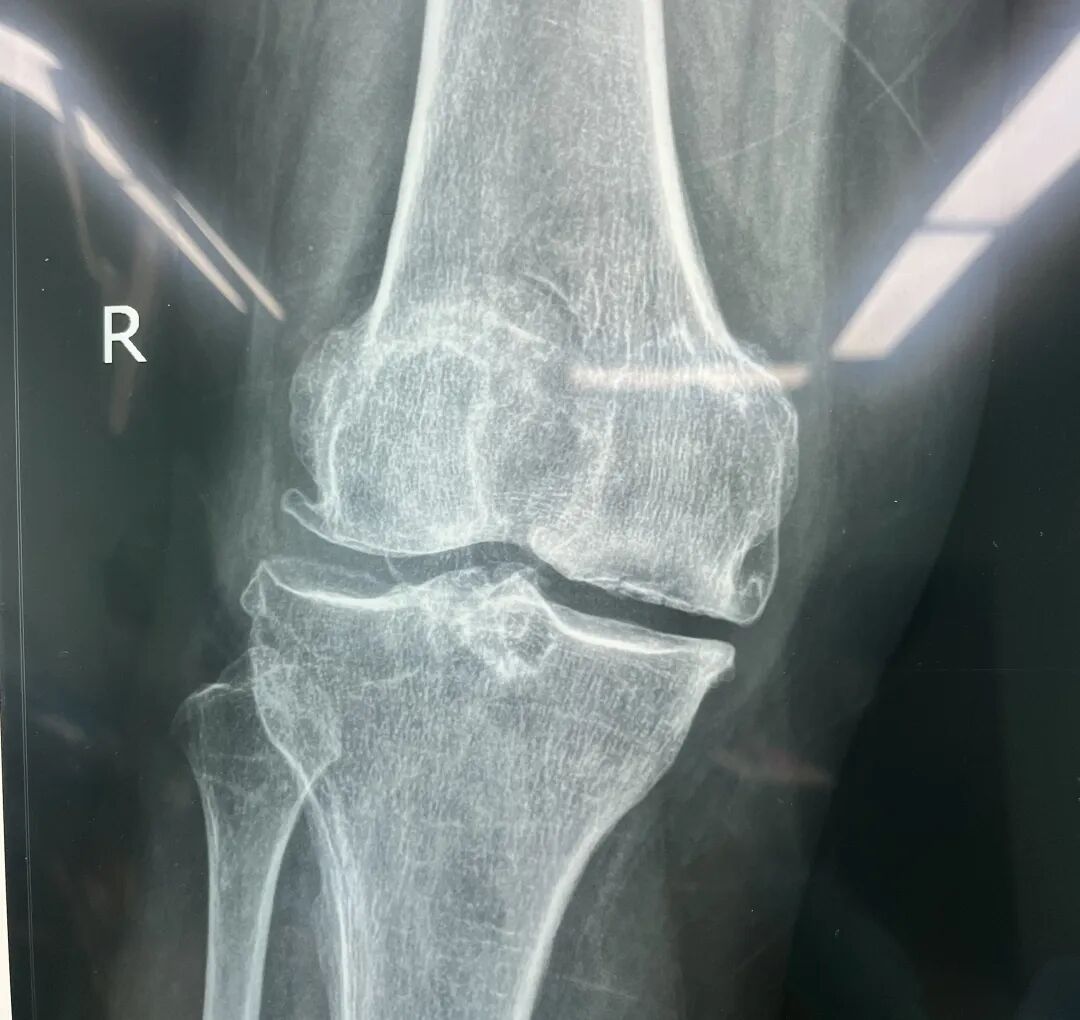

74岁的王奶奶,从十年前,右膝就出现了关节疼痛,近期逐渐加重,站立时感到疼痛难忍,生活质量大大降低。在家人的陪同下,她来到我院骨伤科就诊。主治医师王成接诊后为患者做了DR、CT检查发现,患者右膝骨关节病伴屈曲挛缩,保守的治疗已经很难发挥效果,需进行关节置换。